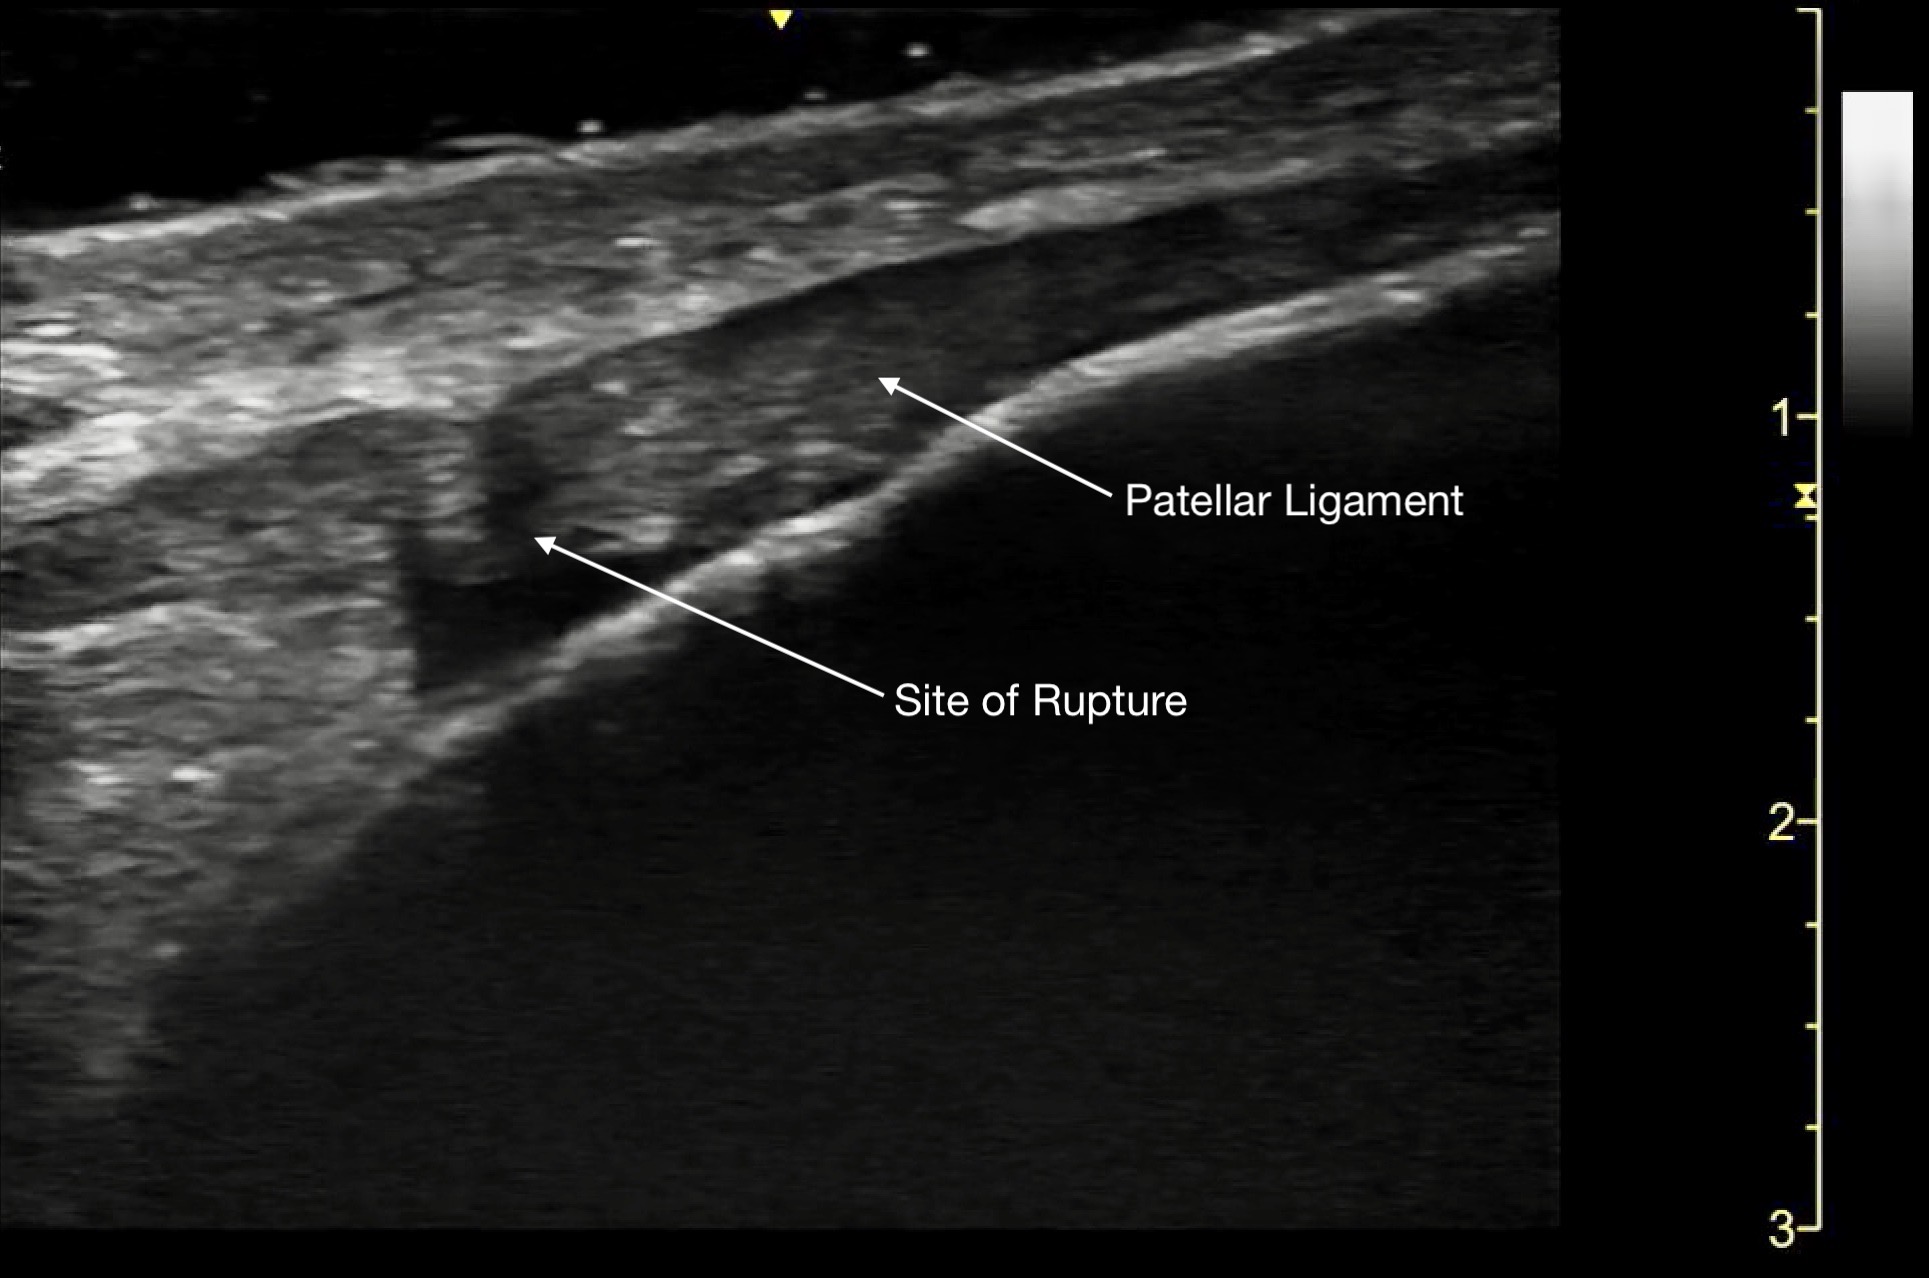

Tendon ruptures appear as areas of hypoechogenicity from edema/hematoma, and adjacent bunched up, retracted tendon fibers. For complete tears, the portion of the tendon near the injury will lose its rigid, straight appearance and instead appear irregular and have a large gap between the torn end and its insertion point. Partial tears are more subtle and will sometimes only have a small, cone-shaped hypoechoic focus. The key with tendon exams is to view them dynamically, having the patient flex and extend the injured joint (if possible).

Figure 13a.

A) Partial rupture of the patellar ligament at the distal insertion

Figure 13b.

a different patient with a complete rupture at the proximal insertion of the patellar tendon. The patella is on the left side of the image, and note the hematoma that wraps around the ruptured end of the tendo